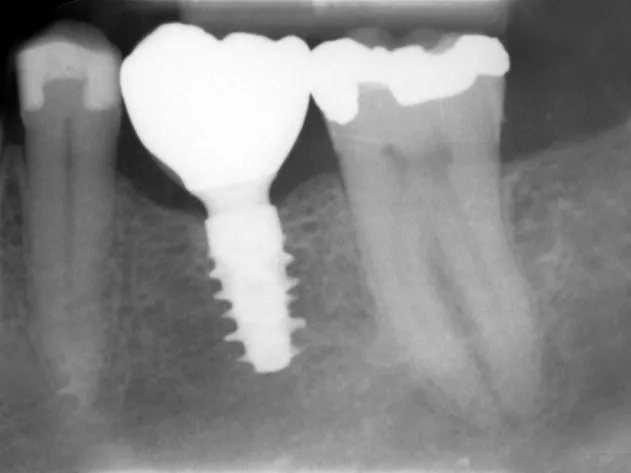

Stable and healthy peri-implant condition (1-year post-op x-ray)

Dr. Eirik Aasland Salvesen, a periodontist at Oris Dental in Stavanger, Norway, and executive director of the Oris Academy, was the responsible surgeon. One year ago, he provided this treatment in a healed mandibular first molar site with the Straumann® BLX implant that was restored prosthetically through analogic workflow in the temporary phase and digital workflow for the final restoration. The circumstances in this case were as follows: A 67-year-old, non-smoking male patient without any relevant medical history, was referred to the office with a missing tooth (#36) due to persistent apical periodontitis. The tooth had been extracted more than one year prior to the procedure and the molar site was well maintained and fully healed.  A CBCT scan showed the patient had favourable bone availability, leading to plans for a one-stage placement of a 5.5 x 10 mm Straumann® BLX implant. After surgically installing the implant, Salvesen allowed the surrounding soft tissue to mature and heal for six weeks. He then removed the healing abutment to begin the prosthetic procedures for a temporary crown.  A stone master cast was made in the laboratory, and a temporary screw-retained PMMA crown was manufactured over a Straumann Wide Base (WB) Temporary Abutment for the crown and placed onto the implant.  After 12 weeks, Salvesen removed the temporary crown, revealing that the soft tissue had healed very well. He then began the digital workflow. For the final crown, a digital impression was made with a 3shape IOS scanner, using a Straumann® Cares scan body. A monolithic zirconia crown was then seated passively onto the implant in a healed and pre-conditioned soft tissue environment. One year after the treatment, the patient reports complete satisfaction with both his chewing function and the overall aesthetics. X-rays confirm that the molar site is stable and healthy. In this first in human case, use of the Straumann® BLX wide implant delivered efficient and reliable performance, even in soft bone with early loading conditions.